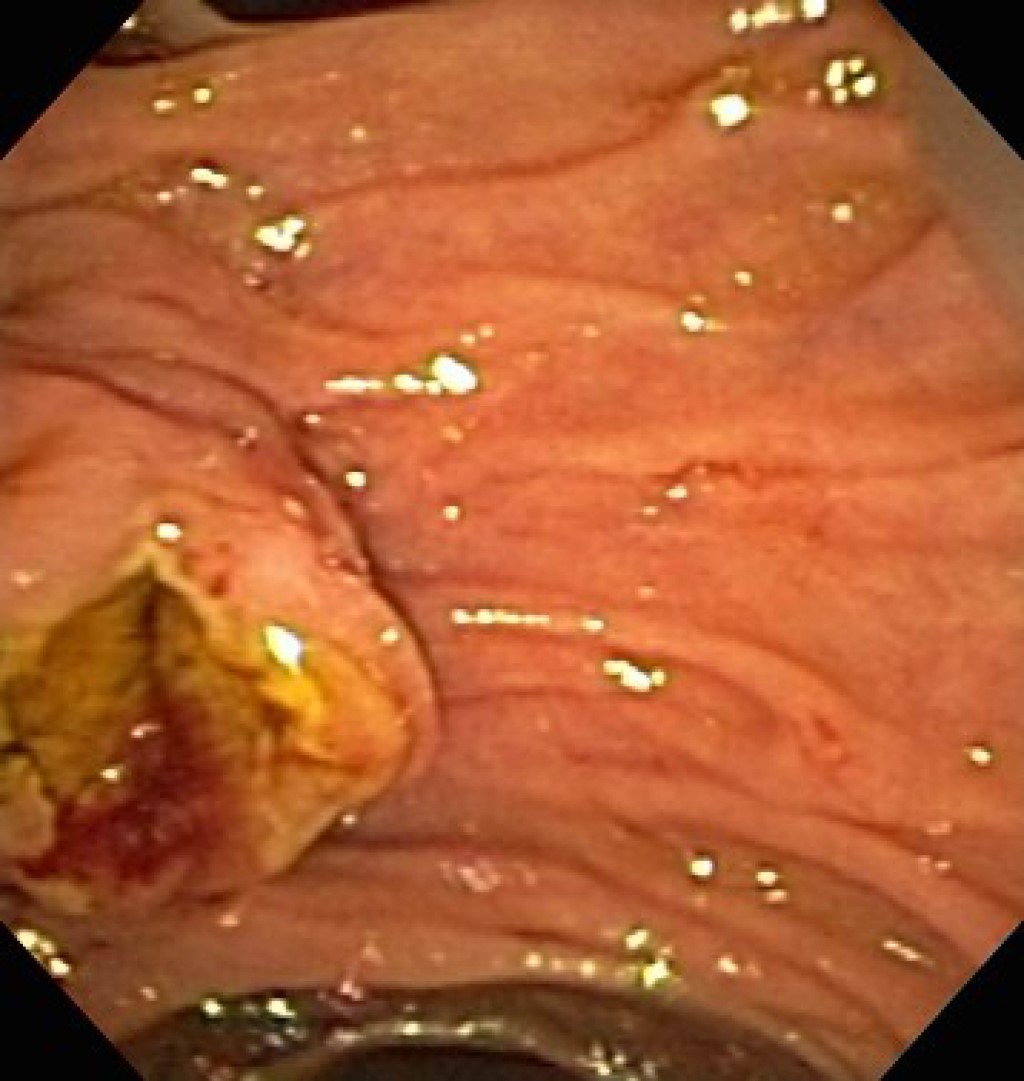

Se colocó a la paciente en decúbito supino con Trendelenburg invertido y bajo efectos de anestesia general, se insertó aguja de Veress en punto de Palmer, se inició neumoperitoneo y se colocó bajo visión directa primer trocar de 15 mm en región supraumbilical paramedial izquierdo seguido de tres trocares más, un trocar paramedial izquierdo de 15 mm colocado de 7 a 10 cm por encima del trocar óptico para la mano derecha del cirujano, trocar paramedial derecho de 5 mm, situado de 7 a 10 cm por encima del trocar óptico para la mano izquierda del cirujano y trocar de 12 mm en hipocondrio izquierdo para el ayudante. Se realizó jareta con PDS 2-0 en antro gástrico y posteriormente incisión gástrica (Figura 2), se insertó a través de gastrostomía el trocar de 15 mm (Figura 3) exteriorizando los hilos de sutura correspondiente a la jareta a través del mismo. El ayudante cirujano y endoscopista avanzó duodenoscopio por medio del trocar de 15 mm hasta segunda porción de duodeno y se observó papila alargada (Figura 4) con múltiples pliegues, posteriormente se canuló de manera selectiva la vía biliar con esfinterótomo y guía de alambre observando avance cefálico de guía, se instiló medio de contraste observando en colangiograma la vía biliar intra y extrahepática dilatada con conducto hepático común y colédoco proximal de 13 mm, colédoco medio 12 mm, colédoco distal de 10.5 mm con un defecto de llenado de 9 mm en su interior. Se realizó esfinterotomía y barrido mediante catéter con balón, se extrajo lito, líquido biliar y contraste. Se infló y ancló catéter con balón, se instiló medio de contraste observando vía biliar permeable sin defectos de llenado (Figura 5). Se procedió a retiro del instrumental con fluoroscopía de control con depuración adecuada de contraste de vía biliar. Se retiró duodenoscopio, se retiró trocar de 15 mm de la gastrostomía y se cerró en dos planos con sutura PDS 2-0 (Figura 6). Se colocó drenaje tipo Blake de 19 Fr hacia la gastrostomía y se exteriorizó por la incisión de trocar en hipocondrio izquierdo, se realizó cierre de heridas por planos y se finalizó el procedimiento sin haber presentado incidentes o complicaciones quirúrgicas. Durante sus primeros dos días de posoperatorio, se mantuvo sin dolor, toleró la vía oral, canalizó gases y el gasto por drenaje escaso con características serohemáticas, por lo que se retiró al segundo día y se decidió su egreso por mejoría, actualmente a varios meses de posoperada se encuentra sin complicaciones.

Figura 4